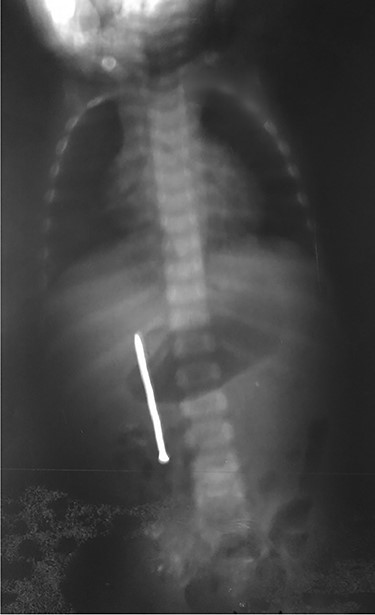

Urgent laparotomy exploration was planned. Intraoperatively, the nail was impacted and palpated through ascending colon wall. The nail was extracted through a minim colic incision centered on its head (Fig. 3), measuring ~6 cm. The ascending colon was mobilized, showing a second part of duodenum anterior wall (Fig. 4) and ascending colon posterior wall perforations (Fig. 5). There was neither peritonitis nor intraperitoneal free fluid. No spillage was noticed in the peritoneal cavity. Intraoperative diagnosis of duodenocolic fistula by nail ingestion was made. All perforations were repaired primarily (by multiple simple interrupted sutures) and drain was placed near repairs (Fig. 6). The follow-up was uneventful. The child was discharged on day 8.

In our case, according to the nail’s position on abdominal radiography, perforations were probably due to duodenal wall extension and progressive erosion of the nail’s head through the duodenal wall [3–5]. Our patient did not present signs of peritonitis neither free peritoneal air (pneumoperitoneum) because the site of duodenal perforation was covered by adjacent loops of ascending colon. This avoids the passage of intraluminal air into the peritoneal cavity.